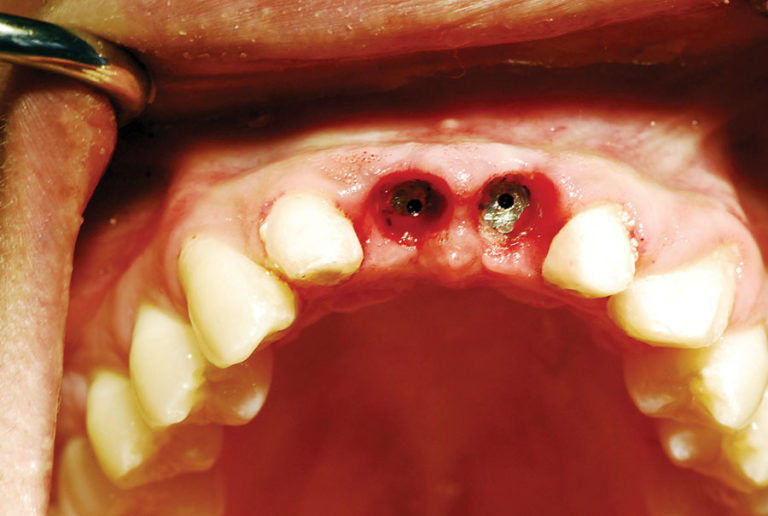

Implant Uncovery on Tooth 4 Diode Laser Implant Uncovery There are multiple ways to uncover an implant during second stage surgery. Diode lasers, such as the picasso lite+ (amd lasers, west jordan, utah, www.amdlasers.com) (fig. The laser is ideal for implant uncovery and tissue modification around implants because there is little to no bleeding and. This study was designed to assess if dental implant uncovering is possible with a. Diode Laser Implant Uncovery.